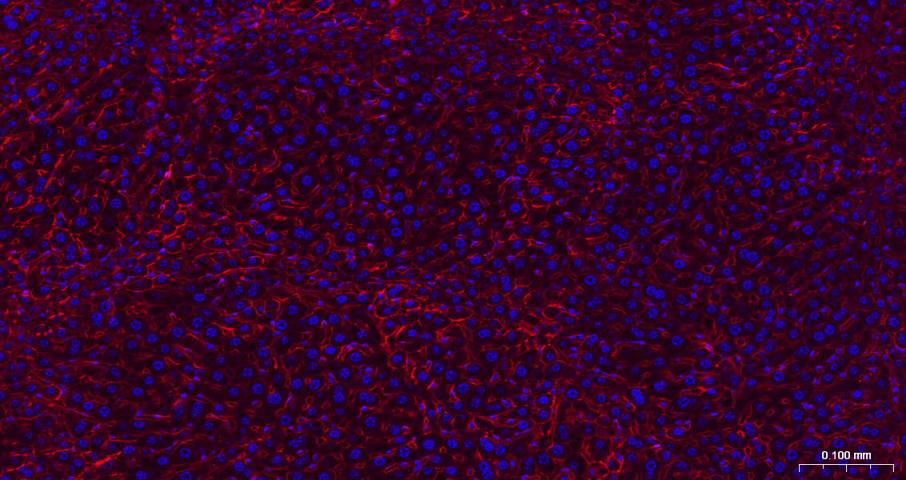

Paraformaldehyde-fixed, paraffin embedded Human Liver; Antigen retrieval by boiling in sodium citrate buffer (pH6.0) for 15 min; The section was incubated with N Cadherin Monoclonal Antibody, Unconjugated (bsm-52389R) at 1:200 overnight at 4°C. Followed by conjugated Goat Anti-Rabbit IgG antibody (Red, bs-0295G-BF594), DAPI (blue, C02-04002) was used to stain the cell nuclei.